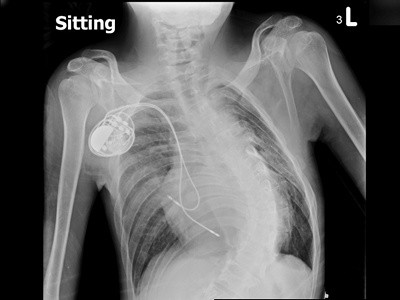

圖:病人徐先生置放心律調節器前(左圖)、後(右圖)的X光檢查圖。

徐先生日前因心跳異常緩慢,每分鐘只有二十至三十下,稍微一動就會「很喘」,由心臟內科張懷仁醫師收治,確診為「完全性房室傳導阻斷」,並建議置放心律調節器。但因徐先生有嚴重胸部脊椎側彎、心臟偏右側、加上心臟血管異常,且患有發生率僅0.3%的「持續性左上腔靜脈」,大幅增加手術的困難度。經過一個月的沙盤推演,張懷仁醫師與醫療團隊於四月中旬成功為徐先生置放心律調節器。徐先生術後復原良好,短短一星期的住院期間,更增胖了2公斤。

為了讓徐先生在最安全的情況下執行手術,張懷仁醫師與醫療團隊近一個月的沙盤推演,多方考量。一般心律調節器的置放,只需施行局部麻醉,考量徐先生的身體狀況,張懷仁醫師與麻醉科合作,讓徐先生在全身麻醉的情況下裝置心律調節器。四月中旬,花蓮慈院醫療團隊成功為徐先生完成心臟節律器置放,手術時間不到三小時,傷口僅三公分。徐先生隔天就轉出加護病房,在普通病房觀察四天後就順利出院,住院期間還增胖了2公斤。